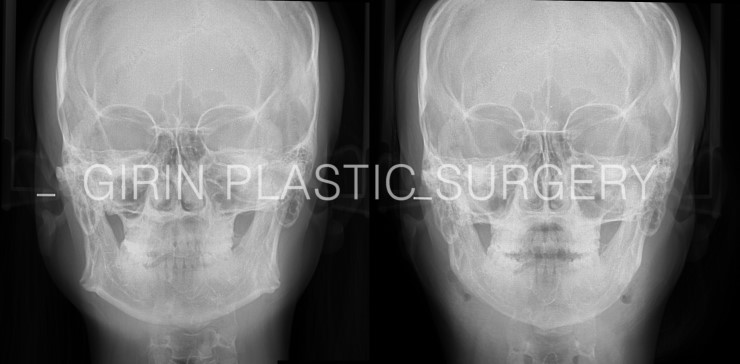

턱이 넓어보이고 얼굴이 커 보이는 원인은 비단 뼈의 문제만은 아닙니다. 뼈, 근육, 구강구조, 지방 등 다양한 원인이 있기 때문에 복합적인 수술계획이 필요합니다. 오늘 소개할 수술사례는 턱뼈가 벌어져있어 수술효과가 아주 좋을 케이스지만 볼살이 많은편이라 추가적으로 심부볼제거를 진행하였습니다.

이십대후반 여성분으로 처음 상담 시 V라인 리프팅을 목적으로 내원하셨는데 이분은 지방제거만으로 만족스러운 V라인효과를 얻기 불가능하기 때문에 뼈수술을 하면 어떻겠냐고 먼저 권해드렸습니다. 수술전 귀밑각이 상당히 벌어져 있는 상태라 수술후 변화가 상당히 큽니다.

정면 엑스레이